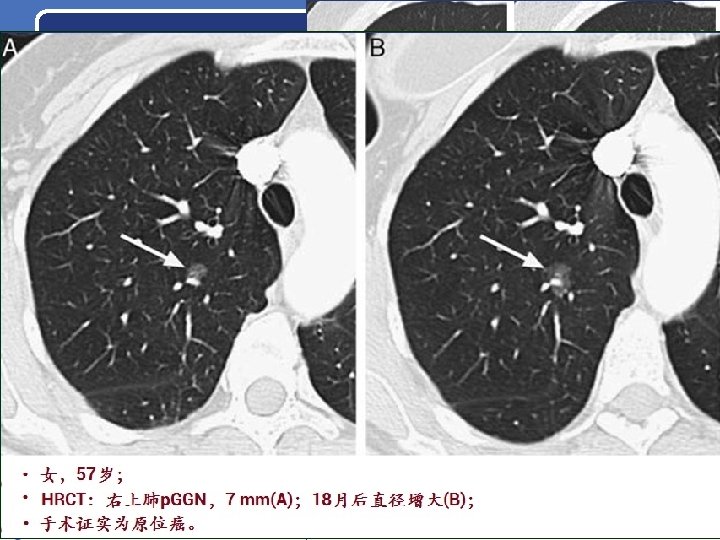

原位腺癌(AIS) LUNG NODULE v 原位腺癌(AIS)多为非粘液性,HRCT上表现为: • p. GGN,密度较AAH略高; • 直径一般> 5 mm; • 少部分AIS因肺泡壁塌陷而呈m.

原位腺癌(AIS) LUNG NODULE v 原位腺癌(AIS)多为非粘液性,HRCT上表现为: • p. GGN,密度较AAH略高; • 直径一般> 5 mm; • 少部分AIS因肺泡壁塌陷而呈m. GGN。 v AIS的预后:很好,手术切除后5年生存率达 100%。 Lee HY, et al. Am J Roentgenol 2014; 202: W 224 -33. Myrna CB, et al. J Thorac Imaging 2012; 27: 240 -6. Travis WD, et al. J Thorac Oncol 2011; 6: 244 -85. Yang ZG, et al. Am J Roentgenol 2001; 175: 1399 -1407. 四川大学华西医院 22